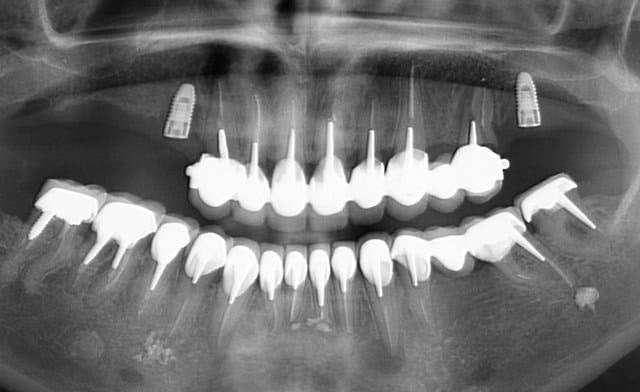

Mon petit cas galère du moment...

Péri-implantite 14 et 26.

25 explosée.

Infection apicale 13, 12, 33 (chaque 2 mois sous antibio depuis pas mal de temps...)

Et gros bouchon de fugy de 2 à 3 mm au fond du logement de l'inlay core, que j'ai dû traverser à la fraise diamantée pour pouvoir retraiter la 13 et la 12... :-)

C'est plus une bouche, c'est une grille de Loto :))

Un loto gagnant alors, parce qu'il y a eu un sacré investissement de fait!

Quand je vois des panos comme ça je me dis : soit c'est un CMU, soit il a une bonne mutuelle.

Bonne mutuelle (450% sans plafond)... mais malheureusement pour elle pas bon dentiste!

Des pano comme ça, j'en vois tous les deux jours, avec des lésions apicales un peu partout.

Là, le dentiste (retraité depuis peu) a tout couronné, mis deux implants en plus pour rien, puis un stellite avec attachement (avec les implants en dessous qui ne servaient à rien...).